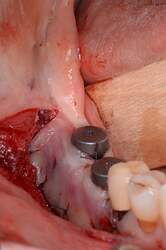

Fig. 4.

Alveolar ridge augmentation of the anterior maxilla. A Initial intraoperative situation with an extended alveolar defect of the anterior alveolar jaw. Two allogeneic cortical bone plates were fixed by fixation screws. B Intraoperative situation after filling the defect with allogeneic spongious granules. C Covering the augmented area with a porcine collagen membrane. D Implant placement 4 months later. E Overlining with xenogeneic bone graft to preserve the volume of the augmented area. F X-ray demonstrating inserted implants